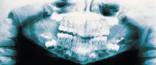

The problem: Examination of the panoramic radiograph revealed a mixed radiolucent-radiopaque lesion. The lesion was seen in association with an unerupted tooth #3.

The problem: Examination of the panoramic radiograph revealed large bilateral, well-defined multilocular radiolucencies.

The problem: Radiographic examination revealed teeth with short W-shaped roots and obliterated pulp chambers

The problem: Examination of the occlusal radiograph revealed a large well-defined radiolucency.

The problem: Radiographic examination of the area revealed a well-defined cyst with corticated borders distal to the roots of tooth #31.

The problem: Oral examination revealed shiny gingiva with a lack of stippling in the area of involvement.

The problem: Radiographic examination revealed mixed lucent-opaque lesions around the apices of teeth #24 and #25.